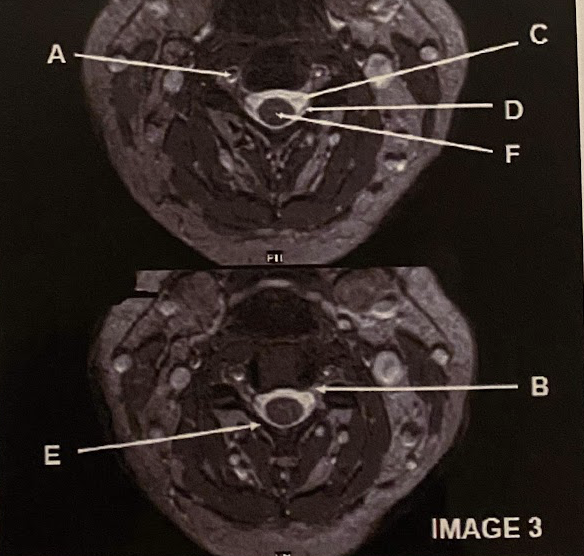

Which letter demonstrates the cervical nerve root exit foramina?

C

What letter demonstrates the intervertebral disc?

B

What letter demonstrates the conus medullaris?

A